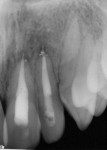

At presentation (Figure 1 through Figure 4), the patient was symptomatic with a dull ache. Teeth Nos. 8 and 9 were repositioned incorrectly, with tooth No. 9 being severely malpositioned. Upon examination, the patient was afebrile and alert and oriented times three. He stated that he did not lose consciousness at the time of the trauma. The patient’s vital signs were determined and considered normal. The patient had no history of significant medical disease, denied all medications, and had no known drug or food allergies. His review of systems was noncontributory for systemic disease. The patient’s head-and-neck examination exhibited no signs of facial fracture. A small laceration of his upper lip in association with tooth No. 9 was healing well. Teeth Nos. 8 and 9 were malpositioned, with tooth No. 9 being severely extruded. The remainder of his head-and-neck examination was unremarkable.

Teeth Nos. 8 and 9 were tender to percussion and palpation. Teeth Nos. 8 and 9 were nonresponsive to cold testing (Frigi-dent™, Ellman International, www.ellman.com). Teeth Nos. 8 and 10 were +1 mobile, while tooth No. 9 was +3 mobile. The gingival tissue around tooth No. 9 was erythematous. Periodontal probing depths were 3 mm to 4 mm generalized for all teeth except tooth No. 9, whose probing depths were 6 mm to 8 mm. Upon radiographic examination, teeth Nos. 8, 9, and 10 had widened periodontal ligament spaces. No other pathology was noted. The remainder of the examination was unremarkable.